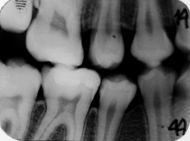

Radiografiile bitewing sunt insa esentiale pentru diagnosticul leziunilor aproximale daca sunt realizate corect, in conditiile in care punctele de contact nu se suprapun si nu exista inghesuire posterioara.

- pozitia retro-dento-gingivala a filmului (f), pozitia in planul ocluzal (muscata) a aripioarei (a) si orientarea fascicului de radiatii (x) in vederea executarii unei radiografii corecte "bitewing" (dupa S.Login).

Leziunea posterioara apare ca o arie triunghiulara intunecata in smalt. Se poate afla pe suprafata externa a smaltului sau in profunzimea acestuia.

- leziune initiala de smalt situata pe fata distala a dintelui 4.5, vizibila ca arie triunghiulara intunecata in externa a smaltului pe radiografia bitewing.